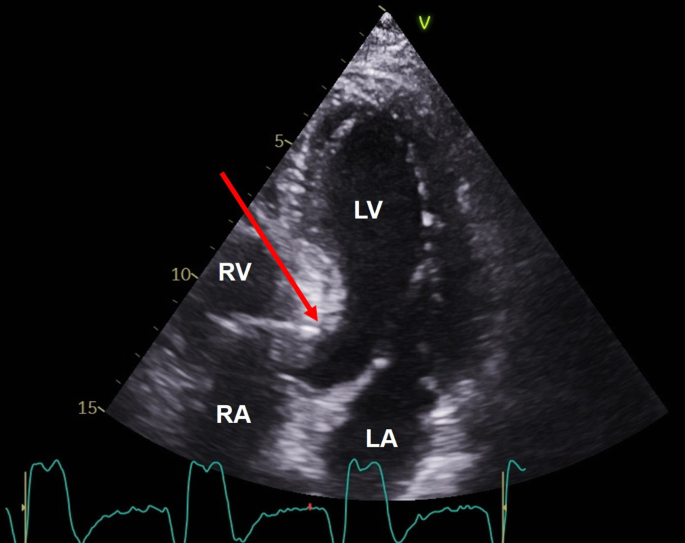

Echo image of right ventricular apex (RVA) pacemaker, pressure

Echocardiography and Heart Failure: A Glimpse of the Right Heart - Pleister - 2015 - Echocardiography - Wiley Online Library

Right ventricular endomyocardial fibrosis – echocardiographic profile with video – All About Cardiovascular System and Disorders

A4C RV focused (Echo) - TECHmED

Frontiers Normal Echocardiographic Reference Values of the Right Ventricular to Left Ventricular Endsystolic Diameter Ratio and the Left Ventricular Endsystolic Eccentricity Index in Healthy Children and in Children With Pulmonary Hypertension

Frontiers Optimization of Left Ventricle Pace Maker Location Using Echo-Based Fluid-Structure Interaction Models